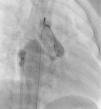

The most frequent symptoms were murmur and/or fatigue. All fistulas were congenital. Five patients (42%) had concomitant cardiac disease: pulmonary atresia with intact ventricular septum (1), patent ductus arteriosus (1), ostium secundum atrial septal defect (1), stenotic bicuspid aortic valve (1), and critical pulmonary stenosis operated in the neonatal period (1). Selective angiography was performed to delineate the anatomy of the fistula(s), which were embolized in the most distal part, sparing all the collateral branches. In one patient an arteriovenous loop was formed through the fistula, embolizing the terminal part of the fistula from the right atrium. The patients were heparinized (100UI/kg in children and 5000UI in adults) and were subsequently monitored by assessing activated coagulation time. Three patients had two fistulas, while the others had a single lesion. All fistulas were hemodynamically significant. They originated in the territory of the right coronary (10), left coronary (3) and circumflex (2), draining into the right ventricle (5), pulmonary artery (6), right atrium (2) coronary sinus (1) and left ventricle (1). Embolization materials included 15 standard coils in three patients, a Jackson® coil in one patient (Figures 1–3), 27 microcoils in 11 patients (18 standard microcoils in seven patients and nine GDC microcoils in four patients), and an Amplatzer® duct occluder in one patient (Figures 4–7). The GDC microcoils, both standard and complex, deserve particular mention, as release of these devices is controlled by electrolysis. The procedure is thus reversible up to the last stage of release, following confirmation of correct positioning. An Amplatzer® cardiac plug was tested in one patient but was not released due to its unsuitability for the lesion.